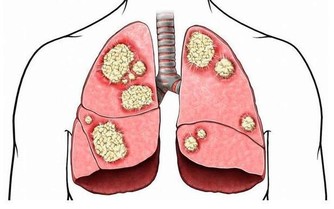

可如果我們的肝臟出現了病變,一開始我們並不能感受到明顯的疼痛。

如果肝臟到了疼痛難忍的時候,那就為時已晚了。

那麼如何在日常生活中,判斷肝臟好不好呢?

發霉食品中的黃曲霉毒素為致肝癌物質,致癌所需時間最短僅為24週,

因此食物應妥為存放,一旦發霉就應立即丟棄,

尤其是黃豆、花生、紅薯、甘蔗等,切不可再食用。

煙中含有的尼古丁和酒的代謝產物乙醇對肝臟來說極其不利,是導致疾病、誘發癌症的主要危險因素之一。